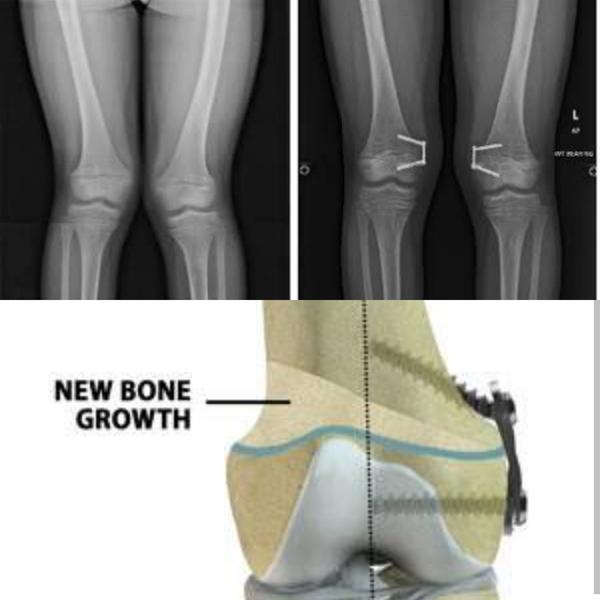

Best guided growth knee surgery for knock knees ,Bend knees in Greater Noida and Noida